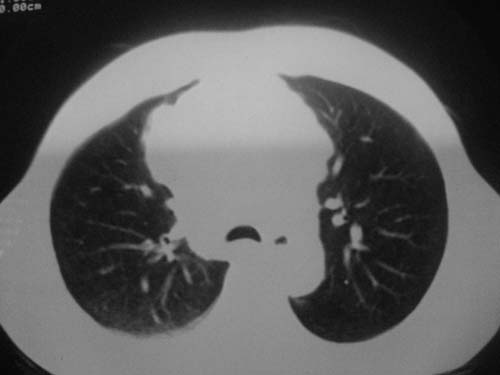

以下是引用科室第一人在2010-3-25 20:30:00的发言:[br]1:纵膈肿瘤性病变,恶性胸腺瘤可能性大伴纵膈右肺门淋巴结转移,右侧胸腔积液。[br]2:右侧肺门肿瘤性病变,纵膈淋巴结转移,右侧胸腔积液。右下叶转移。

以下是引用子期在2010-3-25 21:00:00的发言:[br]先考虑右中央型肺癌伴转移。

以下是引用江广1996在2010-3-25 22:49:00的发言:[br]通常肺癌向纵隔转移多见,纵隔肿瘤向肺内转移少见(有的表现为向肺内侵润)。本例以一元论考虑:右中心型肺癌并纵隔淋巴等多处转移。[br][br][本贴已被 江广1996 于 2010-3-25 22:50:07 修改过]

以下是引用yangyudong333在2010-3-26 6:43:00的发言:[br]“冰冻纵膈”,考虑纵膈淋巴瘤伴肺内及胸膜侵润。